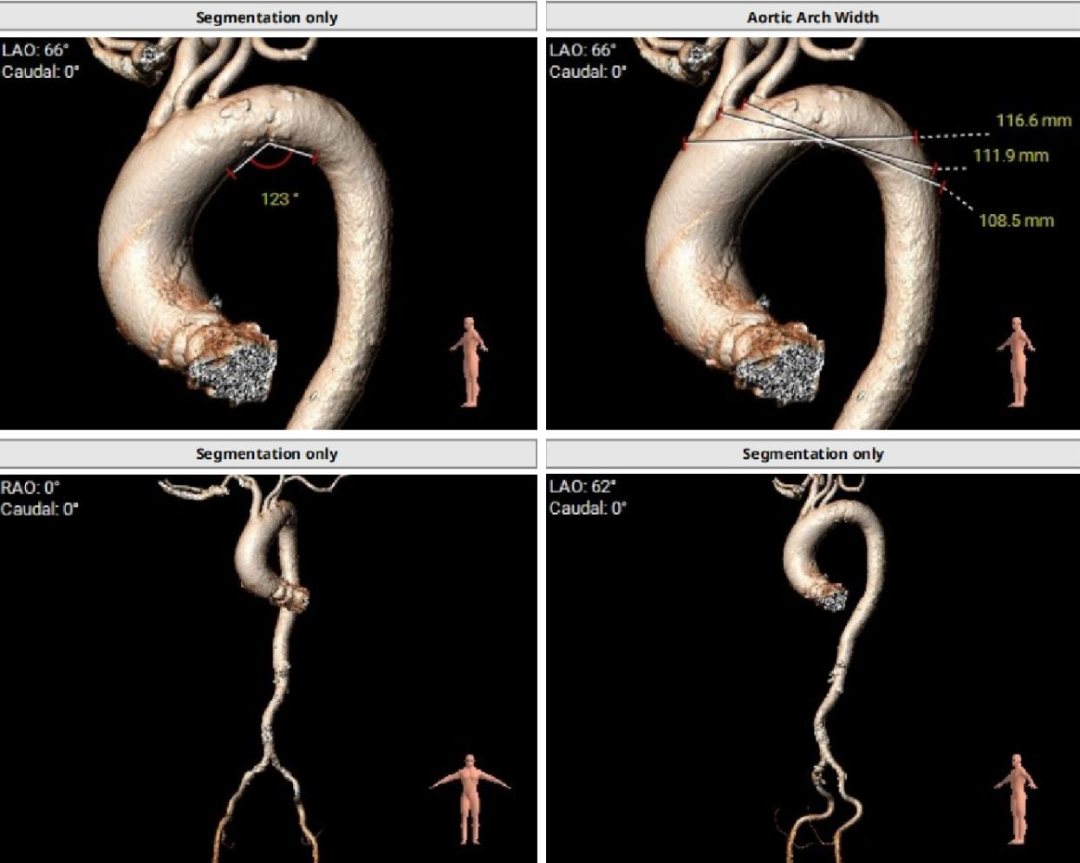

心脏水平夹角67°,横位心;

主动脉弓夹角及弓距可,外周血管入路无明显迂曲。

右侧髂总动脉自发夹层7mm。